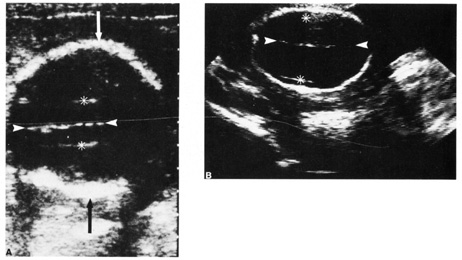

A second trimester ultrasound is usually done at 20 to 22 weeks' gestational age. The most commonly used fetal measurements are biparietal diameter, length of the femur or other long bones, and abdominal and head circumference. In addition to measurements, an anatomic survey is also done to evaluate the fetal brain (Fig. 9), spine, stomach, heart, kidneys, placental location and assessment of amniotic fluid (Fig. 10). If maternal risk factors are present, tetra screening results are abnormal, or there are abnormal findings on the anatomic survey, the patient is sent for a comprehensive ultrasound. The components of a comprehensive ultrasound are shown in Table 9. The ultrasound findings associated with Down syndrome include cardiac defects or enlargement, cystic hygroma (Fig. 11), duodenal atresia (Fig. 12), omphalocele, polyhydramnios, choroids plexus cyst, and renal calyceal dilation.

Fig. 12. Duodenal atresia in a second trimester fetus. A: Ultrasound scan of fetal abdomen (arrowheads) showing two fluid-filled structures (arrows). Increased amniotic fluid (polyhydramnios) surrounds the fetus. B: Newborn radiograph of upper abdomen demonstrating gas-filled stomach (S) and duodenum (D), which are typical findings of duodenal atresia. (Courtesy of Alfred B. Kurtz, MD)